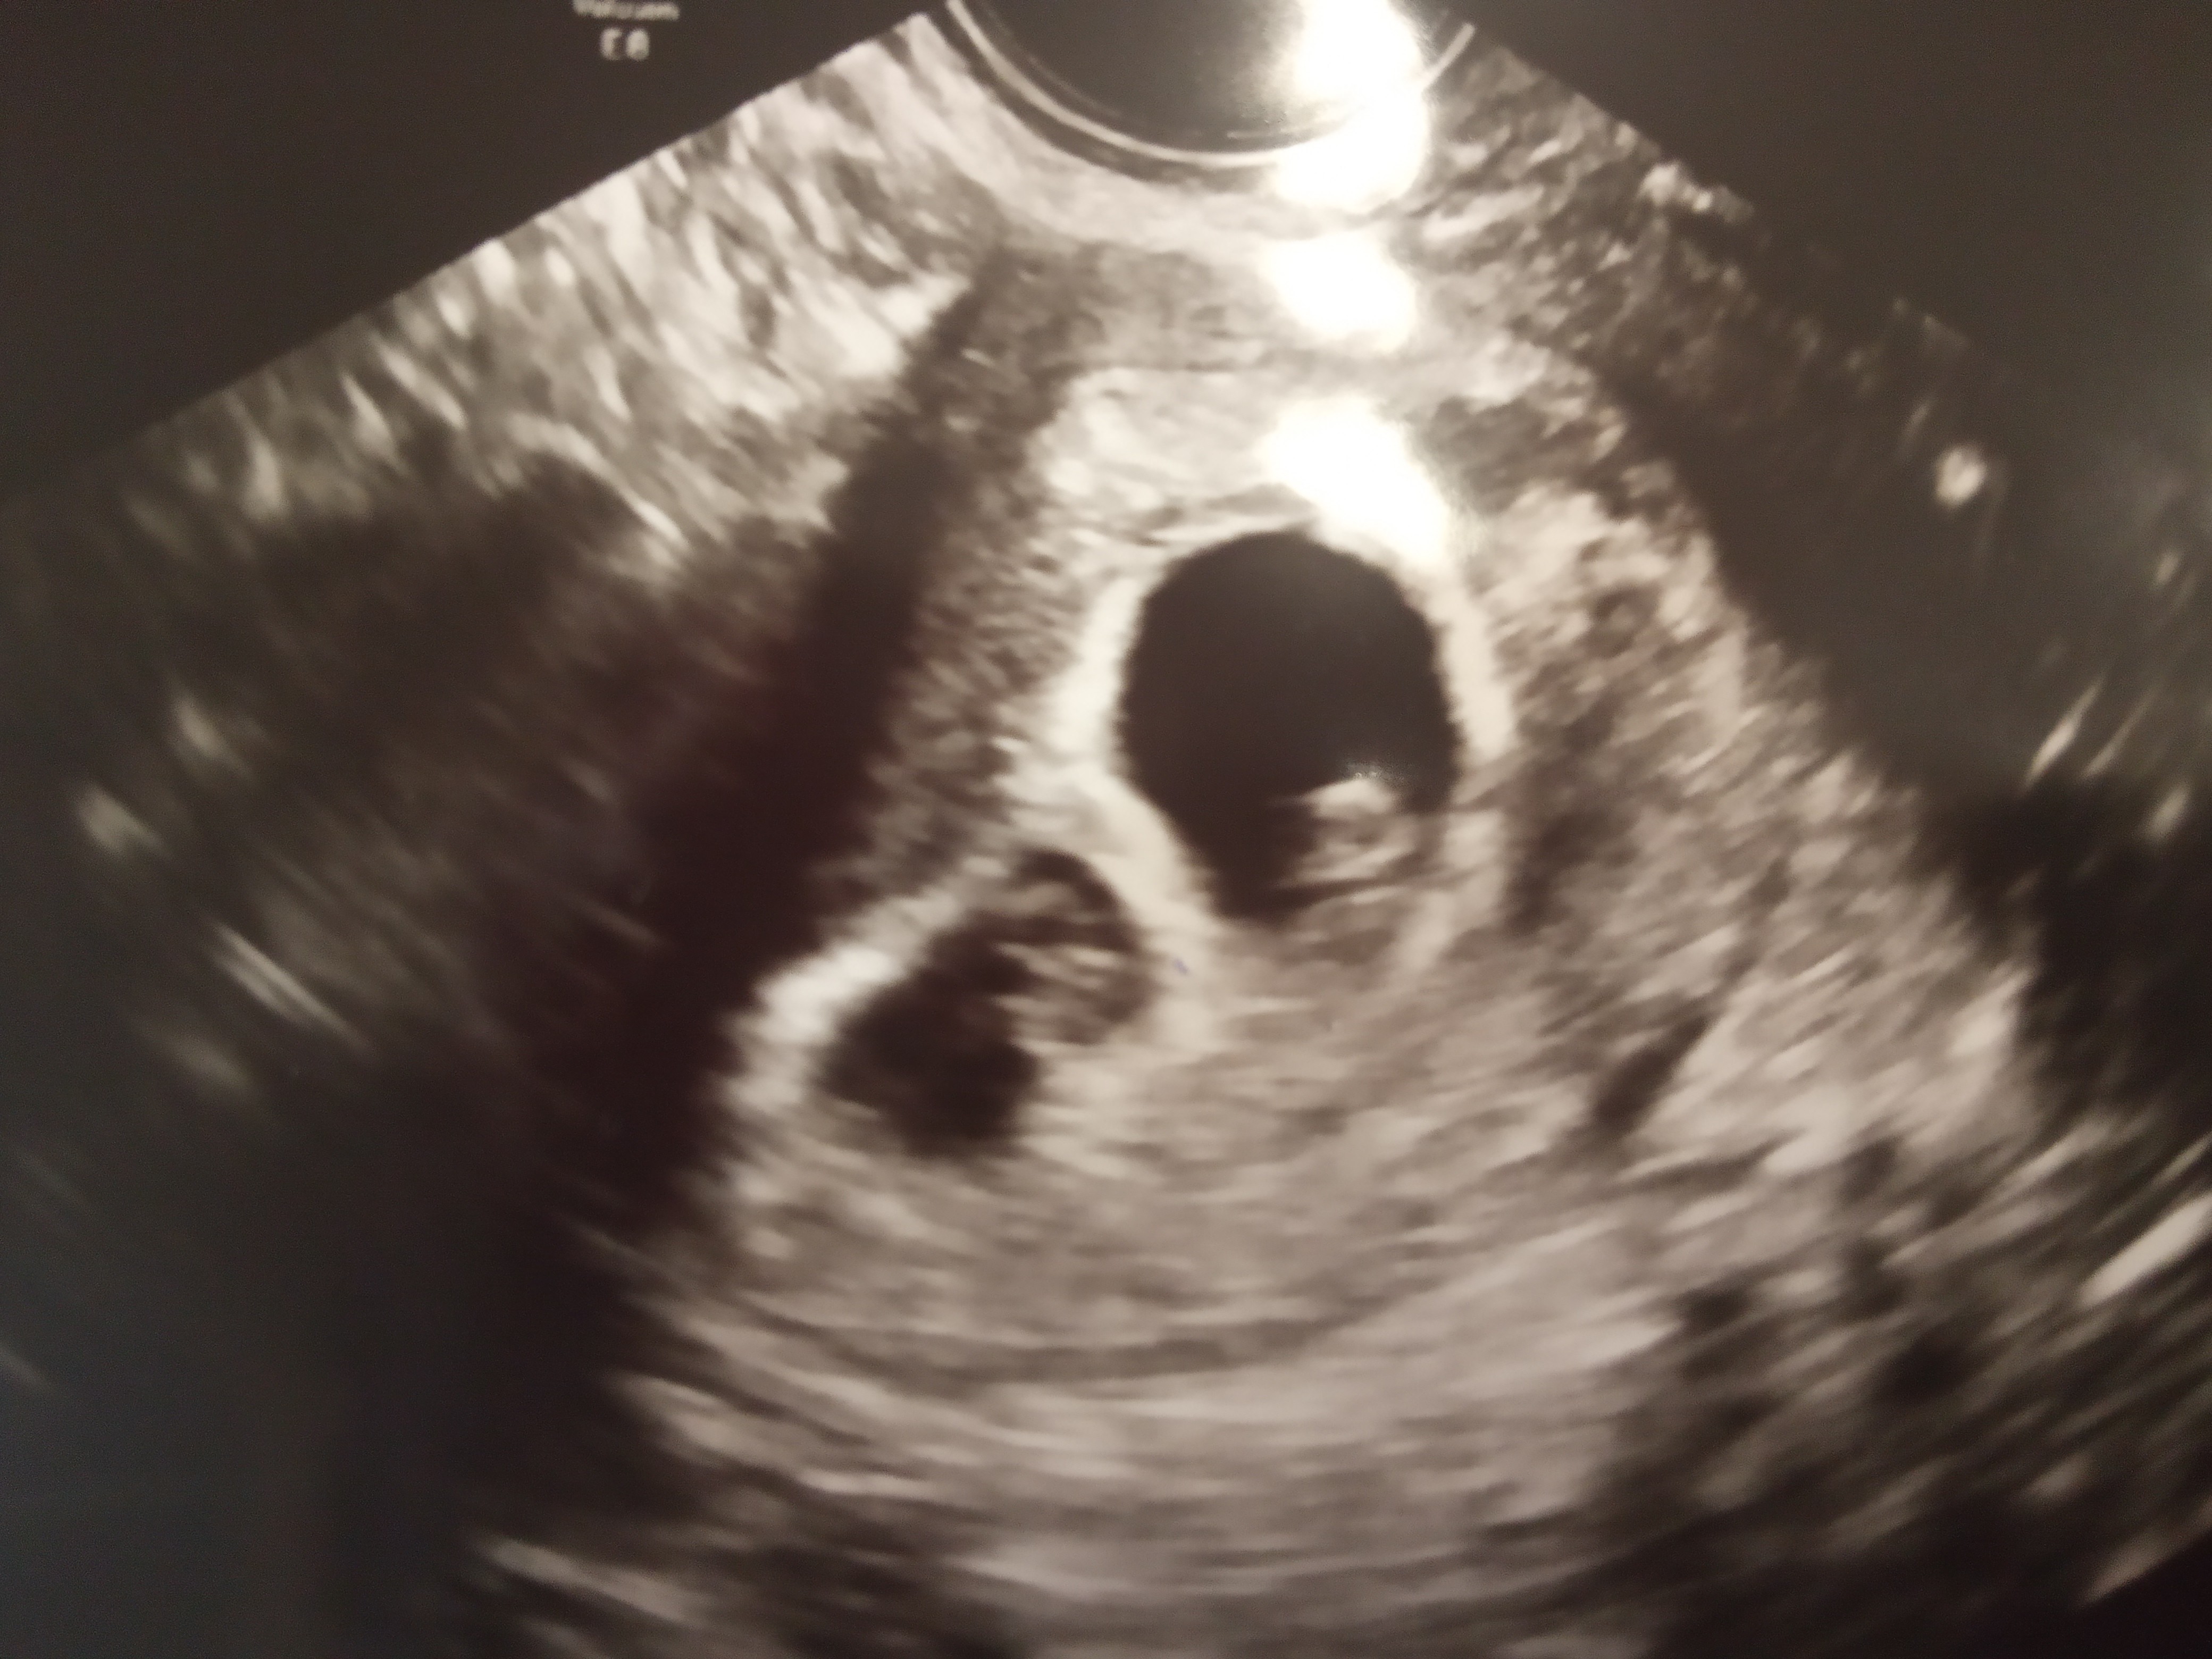

U mnie na razie lekarz stwierdził slabowidoczny pęcherzyk ciążowy prawdopodobnie ciąża bliźniacza.

U mnie 6+0 był jeden pęcherzyk, za dwa tygodnie wyszło, ze są dwa